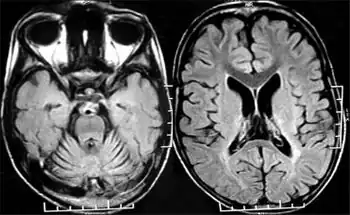

MRI of cranium revealed cerebellar atrophy out of proportion to the cerebral atrophy